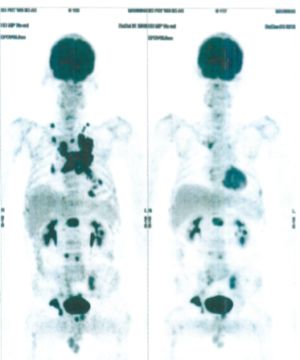

Below are some of the cases, from more than 80 cases we have treated so far with good results. When reading the PET/CT scans, the picture on the left is before treatment, and the picture on the right is after treatment. The intensity of black represents the activity of the cancer, but some black areas are not cancer: brain, heart, radioactive urine in bladder. For the heart, the intensity of black depends on the number of hours of fasting: if more than 10 hours, the heart is not even black, but if fasting is less than 6 hours, it is very black. The intensity of black in the brain can be variable in different scans depending on the brain activity at the time of the scan. The intensity of black in the radioactive urine can also be variable due to the hydration of patients and the time of injection of diuretic.

CASE NO: 3 (PROSTATE CANCER)

A middle-aged man with castration resistant prostate cancer, having failed all currently available cancer treatment, was very weak, and getting worse every day. The PET/CT scan showed he had massive bone metastases. After a few treatment, all the bone metastases went into remission. About 6 months later, he is still in remission.

CASE NO: 4 (PROSTATE CANCER)

A middle-aged man with castration resistant prostate cancer and massive bone metastases, failed all currently available cancer treatment, including with the new and expensive drug XTANDI. After a few treatment, most of the bone metastases went into remission, and the remaining ones are less active. Treatment will continue. Cases no: 3 and 4 show that terminal prostate cancer today can be cured with our new cancer treatment.